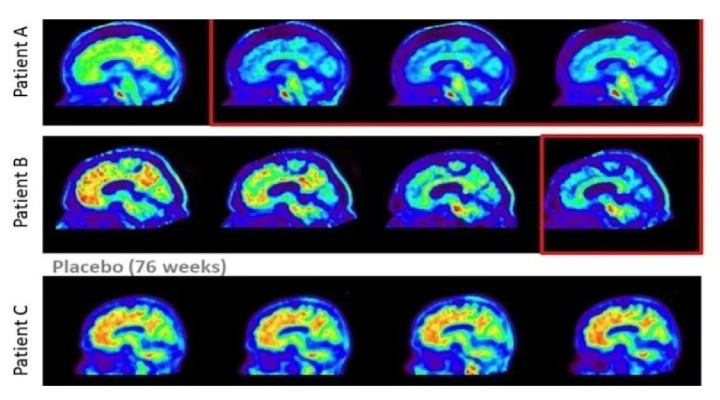

ABD merkezli ilaç ?irketi Eli Lilly’nin geli?tirdi?i donanemab isimli ilac?n “güçlü ve anlaml?” bir sonuç elde etti?i belirtildi. ?irket, yap?lan klinik testler sonucunda elde edilen resmi verileri kamuoyu ile payla?t?.

Yap?lan aç?klamada ?irketin geli?tirdi?i ilac? alan kat?l?mc?larda hastal???n?n ilerleme riskinin yüzde 40 oran?nda azald??? tespit edildi.

Donanemab isimli ilac?n beyindeki pla?a sald?ran bir antikor olarak görev ald??? kaydedildi.